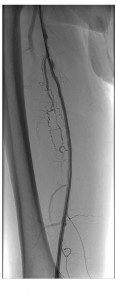

Back to the Patient

Noting both significant lesion length (~18 cm) and ostial location without calcification in our patient, we anticipated that a re-entry device might be successful (if necessary) and proceeded with antegrade probing of the CTO using an 0.035-inch angled Glidewire (Terumo, Somerset, NJ) and Seeker catheter (Bard, Tempe, AZ). As the wire could not be tracked in a straight line, we formed a loop and gently dissected subintimally to just above the knee, at which point we were able to maneuver into the reconstituted SFA.

A single 20-cm length self expanding stent was placed and post-dilated with a good result. Though a re-entry device was readily available, conventional methods proved successful in this case.